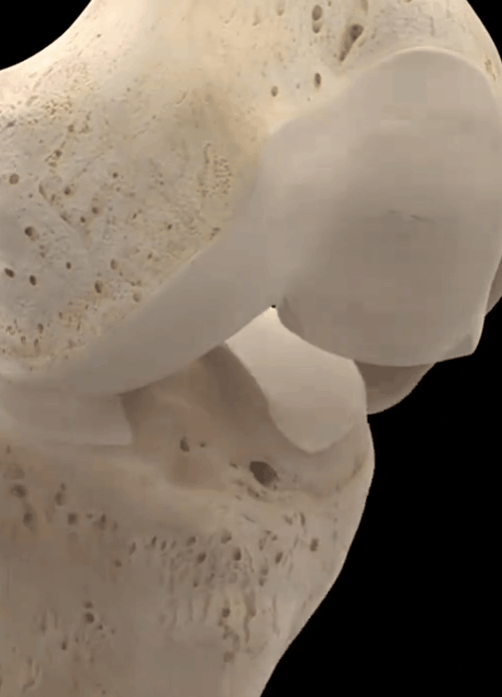

Wie Sie auf dem Bild unten sehen können, ist es typisch, dass sich die Gelenke entwickelt habenSichtbare Lücken, schmale Knochenbildung, einhergehend mit einer schwereren GelenkosteoporoseWenn ein solcher Patient offensichtliche Missempfindungen und Schmerzen hat, wird der Patient durch intraartikuläre Injektionen von Natriumvitrat oder ständige orale Analgetika, die dem Patienten nicht wirklich helfen, das Problem zu lösen, in starke Schmerzen versetzt.

Es wird empfohlen, in solchen Fällen Röntgenaufnahmen des Kniegelenks anzufertigen, um die Möglichkeit einer Arthrose abzuklären. Die Arthrose ist durch folgende Merkmale gekennzeichnet: Sie tritt an gewichtstragenden Gelenken wie den Knien und Hüften auf; die Gelenkschmerzen sind mit Aktivität verbunden und werden durch Ruhe gelindert; nach längerer Ruhe der Gelenke kommt es zu einer vorübergehenden Steifheit und einer lokalisierten Dauer. Danach verschwindet sie für höchstens 30 Minuten; in schweren Fällen treten Gelenkschmerzen und Bewegungseinschränkungen auch in Ruhe auf; die betroffenen Gelenke sind oft von Zärtlichkeit, Knochenhypertrophie, Knochenreibung und bei einigen Patienten von Deformierungen begleitet. Diese Krankheit tritt nicht nur in einem Teil auf, der ganze Körper der Gelenke des Körpers sind möglich Arthritis.

Knie- und Knieschmerzen sind eine häufige Beschwerde bei Menschen mit dieser Erkrankung. Ein frühes Symptom sind Schmerzen beim Treppensteigen und -absteigen, insbesondere beim Abstieg. Sie können ein- oder beidseitig auftreten. Es handelt sich um eine Vergrößerung des Gelenks, die durch eine Hypertrophie des Knochens und eine Ansammlung von Flüssigkeit in der Gelenkhöhle verursacht wird. Eine Synovialhypertrophie ist selten. Schwere Inversionsdeformität des Knies.

- Frikativ--Wenn der Gelenkknorpel stark abgenutzt ist, verlieren die Enden der subchondralen Knochen den Knorpelschutz, und bei direkter Reibung ertönt ein leises, heiseres Reibegeräusch; die in der Gelenkhöhle umherwandernden Knorpeltrümmer verursachen auch leicht ein Einklemmen, was zu einem Gelenkreibungsgeräusch führt. Die Patienten sollten es von einem normalen physiologischen Knacken unterscheiden, das Beurteilungskriterium ist sehr einfach, ein pathologisches Knacken wird oft von Gelenkbeschwerden begleitet.